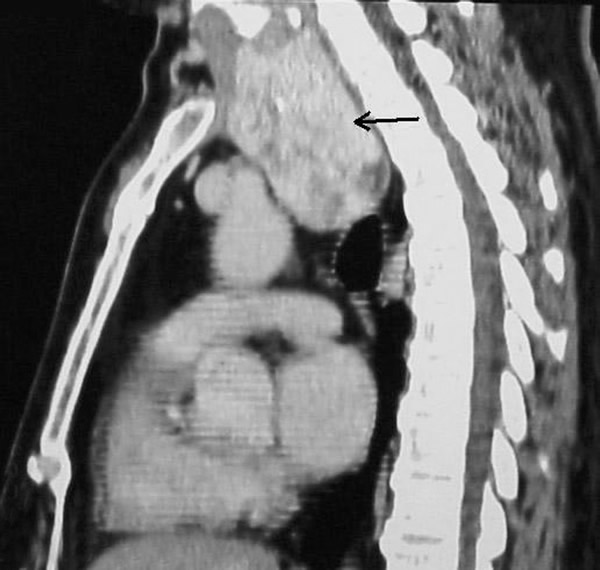

A 58-year-old Chinese man presented with a dry cough of three months’ duration. A chest x-ray at a local hospital revealed "a shadow in the superior mediastinum." A subsequent CT scan suggested "ectopic intrathoracic thyroid" (Figures 1 and 2). His physical examination revealed normal temperature and heart rate, without any signs of hyperthyroidism. Palpation of the neck revealed a non-tender, firm, fixed, and non-pulsatile 2 cm right inferior thyroid mass. A repeat chest x-ray confirmed a mass in the right anteromedial mediastinum, with smooth margins, tracheal compression, and deviation of the trachea to the left (Figure 3). Nuclear Tc99 thyroid scan revealed a cold nodule in the right inferior thyroid gland extending below the sternum (Figure 4). The values of total thyroxin 3 (TT3), total thyroxin 4 (TT4), free thyroxin 3 (FT3), free thyroxin 4 (FT4), and thyroid stimulating hormone (TSH) were all normal. Due to the suspicion of malignancy and to avoid the development of tracheomalacia, surgery was performed to remove the mass.

Figure 3: The arrow indicates the right upper mediastinal mass, trachea compressed. Figure 4: The arrow indicates the “cold” mass of right inferior thyroid that extends into the thorax.